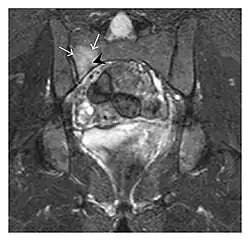

Proximal femoral fractures usually occur in osteoporotic patients, and their signs include subtle neck angulation, trabecular angulation, and subcapital impaction line. A frog-leg lateral view may be helpful if the greater trochanter is short enough. However, positioning can be difficult because of hip pain. In patients with strong suspicion of proximal femoral fracture and negative radiographs, MRI limited to coronal T1 W images and scintigraphy can be highly valuable (Figures 13 and 14). Such an option, with limited examination time, is cost-effective and allows reliable exclusion or confirmation of the diagnosis, preventing an unnecessary stay at the hospital or delayed treatment. Moreover, MRI helps to detect soft tissue abnormalities which are more frequently seen in femoral, acetabular, and pubic injuries than sacral lesions. Concomitant fractures are also frequently seen in typical pelvic sites.[1]

-

a -

b

Figure 13: Partial osseous avulsion of the gluteal muscles at the greater trochanter in a 59-year-old man who presented with the right hip pain without a history of trauma. Lauenstein view and anteroposterior and radiographs (not shown) did not show an obvious fracture line or disruption of bony contours in the acetabulum or the right femoral neck. (a) Coronal T1-weighted MRI displays an incomplete fracture line extending partially from the greater trochanter (arrow). (b) Coronal short tau inversion recovery MRI shows heterogeneous hyperintensity in the same region (arrow) as well as hyperintensity within the gluteus medius and minimus muscles (arrowheads) consistent with tissue edema and hematoma.[1]